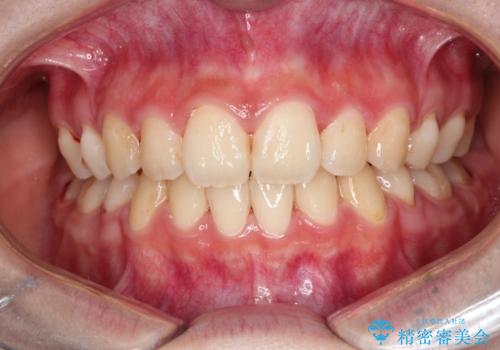

- 口元が出ていることを主訴に来院されました。

歯を抜いてスペースを作ることで、前歯を下げることができました。

ハーフリンガルということで治療期間が3年近くかかりましたが、口元もしっかり下がり満足していただきました。